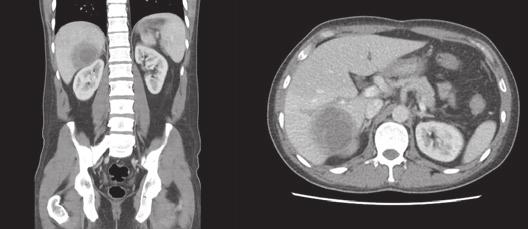

U pacienta je nastavena empirická antibiotická terapie cefotaximem a metronidazolem. K ozřejmění nálezu je doplněnoCTbřicha,kdejepotvrzenadiagnóza

Obr. . CT b icha v sagitálním a transverzálním ezu s potvrzením abscesového ložiska. (Zdroj: Gastroenterologické odd lení, Nemocnice eské Bud jovice, a.s.)

Fig. . CT of the abdomen in sagittal and transverse sections with confirmation of abscess deposit. (Source: Gastroenterology Department, Hospital eské Bud jovice, a.s.)